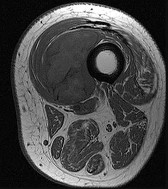

Question 4:

A 32-year-old female presents with progressive knee pain. Imaging reveals an eccentric, lytic epiphyseal-metaphyseal lesion of the distal femur. A biopsy demonstrates multinucleated giant cells in a background of mononuclear stromal cells. If neoadjuvant medical therapy is utilized prior to curettage, the mechanism of action of the most appropriate drug is:

Explanation:

The diagnosis is Giant Cell Tumor (GCT) of bone. Denosumab is a monoclonal antibody often used in the medical management of GCT. Its mechanism of action is the inhibition of RANK ligand (RANKL). In GCT, the neoplastic cells are the mononuclear stromal cells, which express RANKL. This recruits and activates the non-neoplastic, multinucleated osteoclast-like giant cells that cause the massive bone resorption.